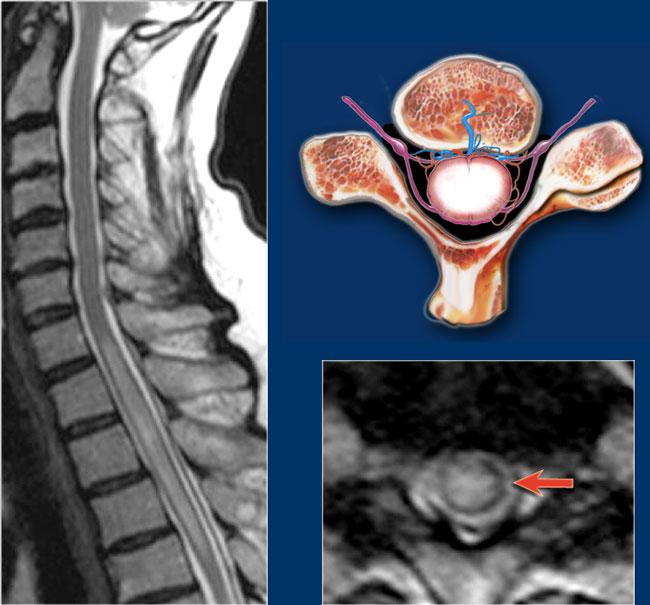

MS thường có hình dạng tam giác và chủ yếu nằm ở phía lưng hoặc phía bên.

Hình ảnh cắt ngang cho thấy vị trí ở phía lưng và hình dạng tam giác điển hình.

Trên hình ảnh cắt ngang, các tổn thương MS thường có hình tròn hoặc hình tam giác và nằm ở phía sau hoặc phía bên.

MS là bệnh “bắt chước vĩ đại” và cũng có thể nằm ở phía trước như ở bệnh nhân này, người có tổn thương ở vị trí điển hình (mũi tên xanh) nhưng cũng có tổn thương ở phía bụng của tủy (mũi tên đỏ).

Trên hình ảnh cắt ngang thấy một tổn thương phía lưng hình tam giác điển hình.